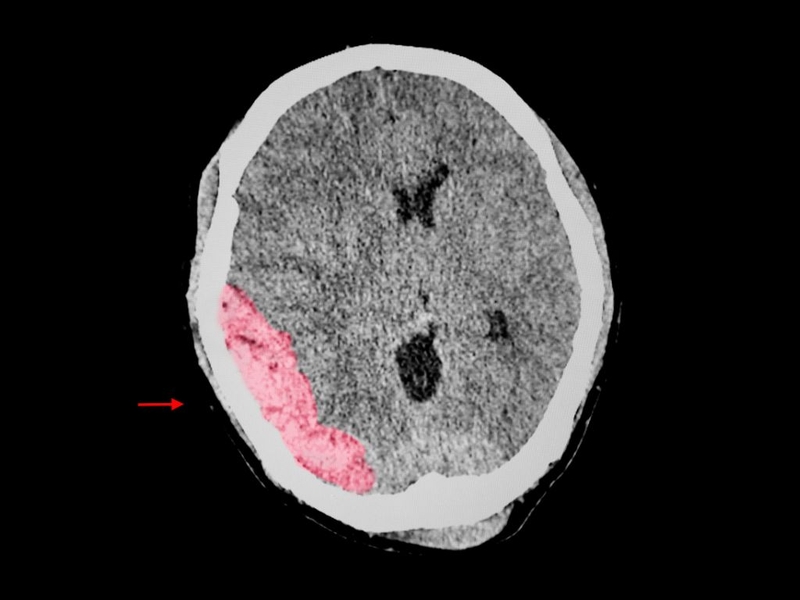

Chấn thương sọ não là tình trạng tổn thương xảy ra khi lực tác động mạnh lên đầu, dẫn đến tổn thương não hoặc mô mềm xung quanh. Các loại chấn thương sọ não phổ biến bao gồm:

Chấn thương sọ não có thể gây ra các triệu chứng nghiêm trọng như mất ý thức, đau đầu, chóng mặt, buồn nôn và đôi khi có thể dẫn đến hôn mê hoặc tử vong nếu không được điều trị kịp thời.